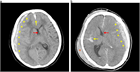

急性硬膜下血腫

1. 頭部外傷受傷直後から片麻痺等の神経症状や意識障害が持続する場合には、急性硬膜下血腫の存在を想起し呼吸・循環管理を行いつつ速やかに頭部CT撮影を行い診断する。